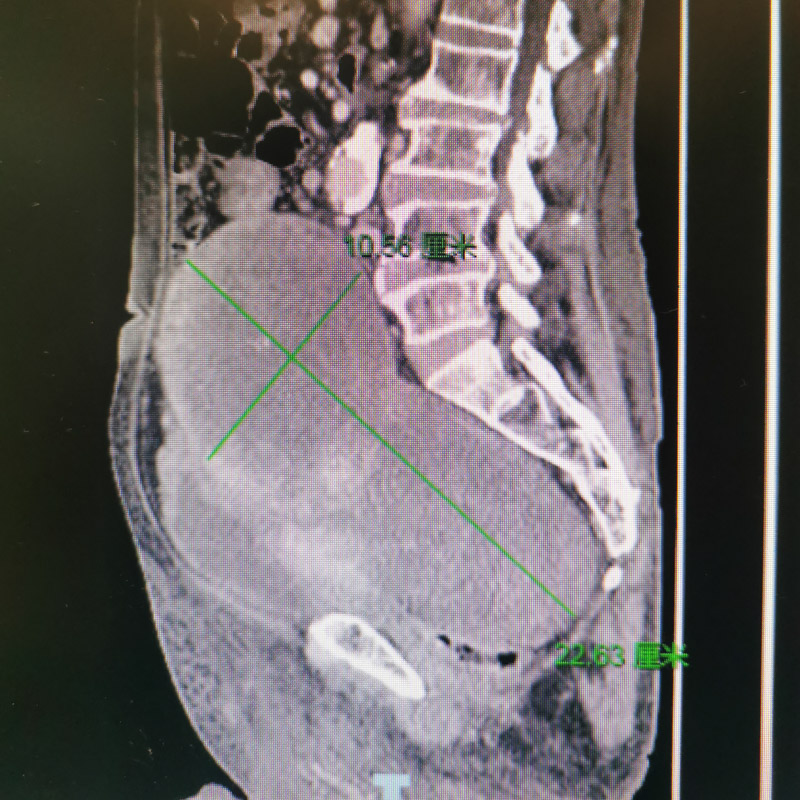

經下肢靜脈彩超、盆腔磁共振及增強CT檢查,提示患者盆腔內有一顆供血豐富的腫瘤,由于腫瘤過于巨大,造成直腸、膀胱及雙側髂靜脈受到了不同程度的壓迫。

近日,柳州市人民醫院血管外科成功為一名盆腔巨大腫瘤患者實施了腫瘤血管栓塞術和盆腔巨大腫瘤切除術,腫瘤重達4斤!大小約23cm*18cm*10cm,為患者解除了腫瘤壓迫癥狀,成功解除了身體和心理負擔。